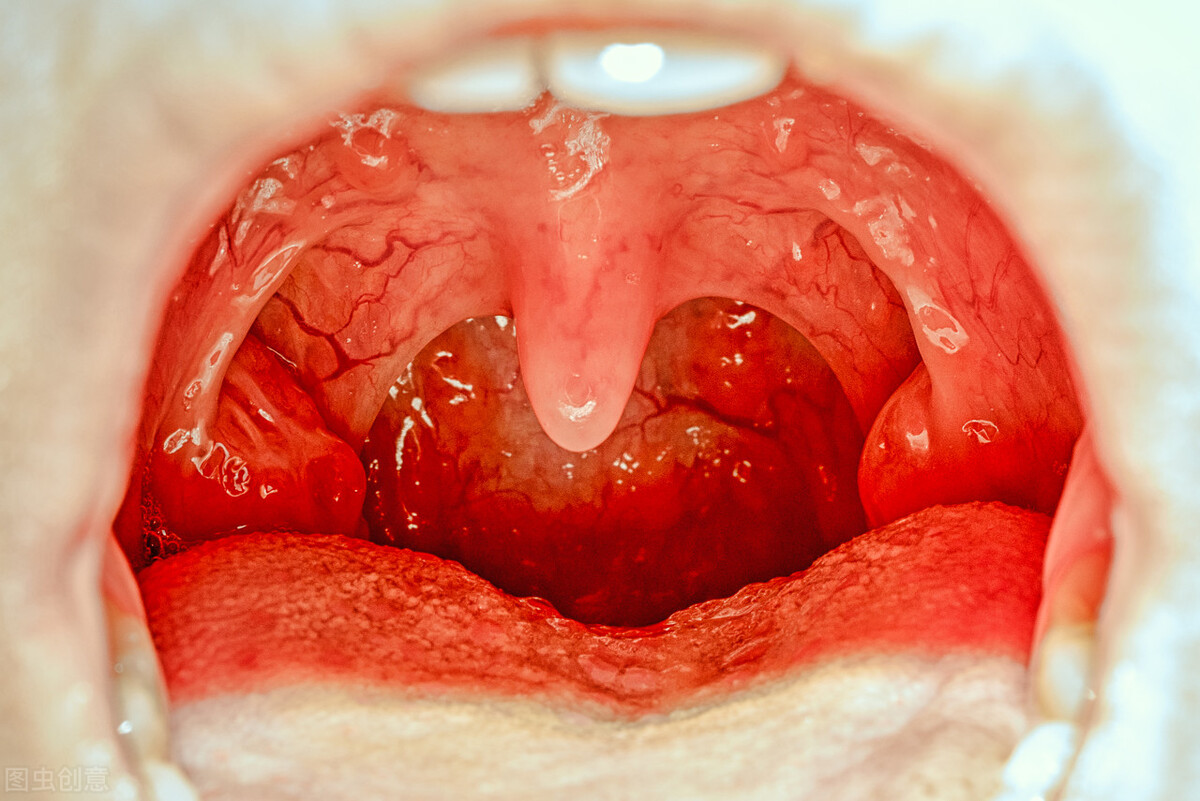

我们常说的扁桃体发炎是指腭扁桃体的急性非特异性炎症。常继发于上呼吸道感染,可伴有不同程度的咽部黏膜和淋巴组织的急性炎症,是一种很常见的咽部感染性疾病。特别是多发于儿童及青少年。

扁桃体炎临床上分为急性和慢性两种,炎症类型不同,症状表现也不相同。

1、急性扁桃体炎的症状表现

● 全身症状起病急,畏寒,高热可达39°~40°,尤其是幼儿可因高热而抽搐、呕吐等。

● 局部症状咽痛明显,吞咽时尤甚,剧烈疼痛者可放射至耳部,儿童若因扁桃体肥大影响呼吸时,可妨碍其睡眠,夜间常惊醒。

扁桃体炎反复发作可导致扁桃体周围脓肿,脓肿破裂严重者会阻塞呼吸道而妨碍呼吸,感染也能扩散到颈部和胸部。

扁桃体炎可引起各种并发症,如中耳炎、鼻窦炎、风湿热、肾小球肾炎、风湿性心脏病、风湿性关节炎等多种疾病,导致心脏、肾脏、关节等方面的严重损害。